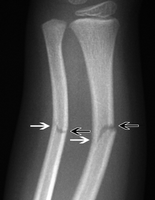

Fig 1: Greenstick fracture

It is an incomplete fracture in which there is a transverse fracture line causing disruption of the outer layer of a bone (cortex), extending onto the core or medulla of the bone without disrupting the opposite cortex. Thus the discontinuity is on one side only. [2]